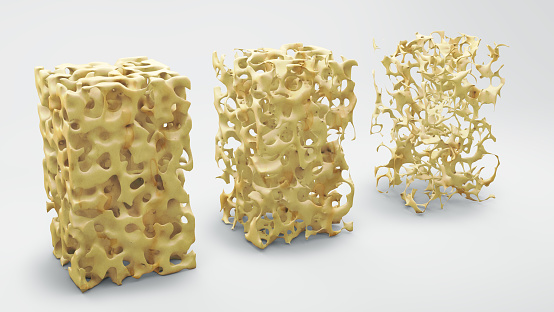

If you’re over the age of 50, then bone health is a serious concern—even more so if you’re a woman. When a person develops osteoporosis, their bones become weak and brittle, which increases the risk of fractures. Osteoporosis also negatively impacts mobility and can lead to isolation and depression. Osteoporosis is often called “the silent ...click here to read more